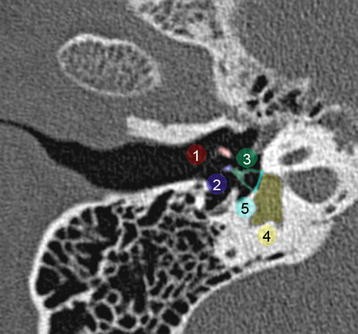

Ct scans can help determine a diagnosis early. Ct and mr of temporal bone malignancies primary and. Ct scan of normal temporal bone, photographed in bone window.

Cn7,ds, cn vii, descending mastoid segment;